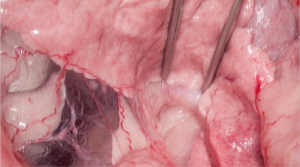

Se realizó la disección del lóbulo izquierdo y el cuerpo del páncreas, usando un sellador vascular/tisular, hasta una porción macroscópicamente libre de lesión. Se continuó con la disección de la vena porta y la vena gastroduodenal. A continuación, se colocaron tres torniquetes de Rummel (en la vena porta craneal y caudal a la invasión y en la vena gastroduodenal) y se procedió a realizar la venotomía de la vena porta y ligadura completa de la vena gastroduodenal al estar en la zona de la venotomía. De esta manera, se liberaron la porción del páncreas diseccionada y el trombo tumoral que invadía la vena porta. El cierre venoso se efectuó con sutura continua con polipropileno 6/0 USP y con hemoclips; después, se colocó un apósito de colágeno (vídeo 2).

Vídeo 2. Procedimiento quirúrgico completo. Pancreatectomía en bloque del lóbulo izquierdo, del cuerpo del páncreas y venotomía de la vena porta para retirar el trombo tumoral: disección del lóbulo izquierdo y cuerpo del páncreas con sellador vascular/tisular (y sección del páncreas en zona sana macroscópicamente), disección de la vena porta y la vena gastroduodenal, colocación de tres torniquetes de Rummel (en la vena porta craneal y caudal a la invasión y en la vena gastroduodenal), venotomía de la vena porta y ligadura completa de la vena gastroduodenal (ya que interfería con la zona de la venotomía), liberando así la porción del páncreas diseccionada y el trombo tumoral que invadía la vena porta. El cierre de la vena fue realizado con sutura continua con polipropileno 6/0 USP y con hemoclips, y después se colocó un apósito de colágeno.